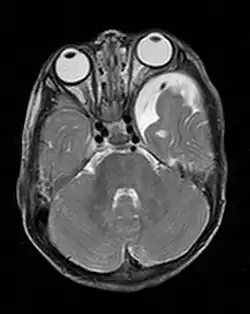

Gliome

Den Großteil der bei Neurofibromatose Typ 1 auftretenden Gliome machen die im Bereich des Sehnervs (Nervus opticus) lokalisierten gutartigen pilozytischen Astrozytome aus, die bei dieser Lokalisation auch als Optikusgliome bezeichnet werden. Bei der Neurofibromatose Typ 1 treten Optikusgliome charakteristischerweise bilateral auf und betreffen so beide Sehnerven. Optikusgliome können bei Patienten mit Neurofibromatose Typ 1 einen über viele Jahre statischen Verlauf haben. Andere Gliome, die bei Neurofibromatose Typ 1 vermehrt auftreten, sind manche Astrozytome und das bösartige Glioblastom.

ZNS-Tumoren (zum Beispiel das Pilozytische Astrozytom bei NF 1 und das Schwannom bei NF 2) und neurologische Symptome treten als ernstzunehmende Probleme der Neurofibromatose auf. Vor allem Tumoren der Hirnnerven können chirurgische Interventionen notwendig machen. Akustikus- und Trigeminus-Neurinome, die vorwiegend bei NF 2 auftreten, verursachen besonders Hörverlust, aber auch Schmerzen. Ein Foramen-Jugulare-Syndrom und Hypoglossus-Tumoren bewirken entsprechende Symptome, ein Optikus-Gliom kann eine einseitige Blindheit und Tumoren der Spinalwurzeln können Lähmungen und Schmerzen verursachen. Darüber hinaus werden verschiedene neurologische Symptome beschrieben: Betroffene Kinder haben oft einen niedrigen IQ, eine ADS oder ADHS, Probleme mit der Selbstorganisation, Motorik-Schwächen sowohl fein- als auch grobmotorisch, dadurch Schulschwierigkeiten, eher selten eine Epilepsie und bei Hypothalamus-Hamartomen eine Pubertas Präcox. Bei Auftreten von epileptischen Anfällen bei Patienten mit einer Neurofibromatose, kann dies als Zeichen dafür gelten, dass sich ein Hirntumor entwickelt.